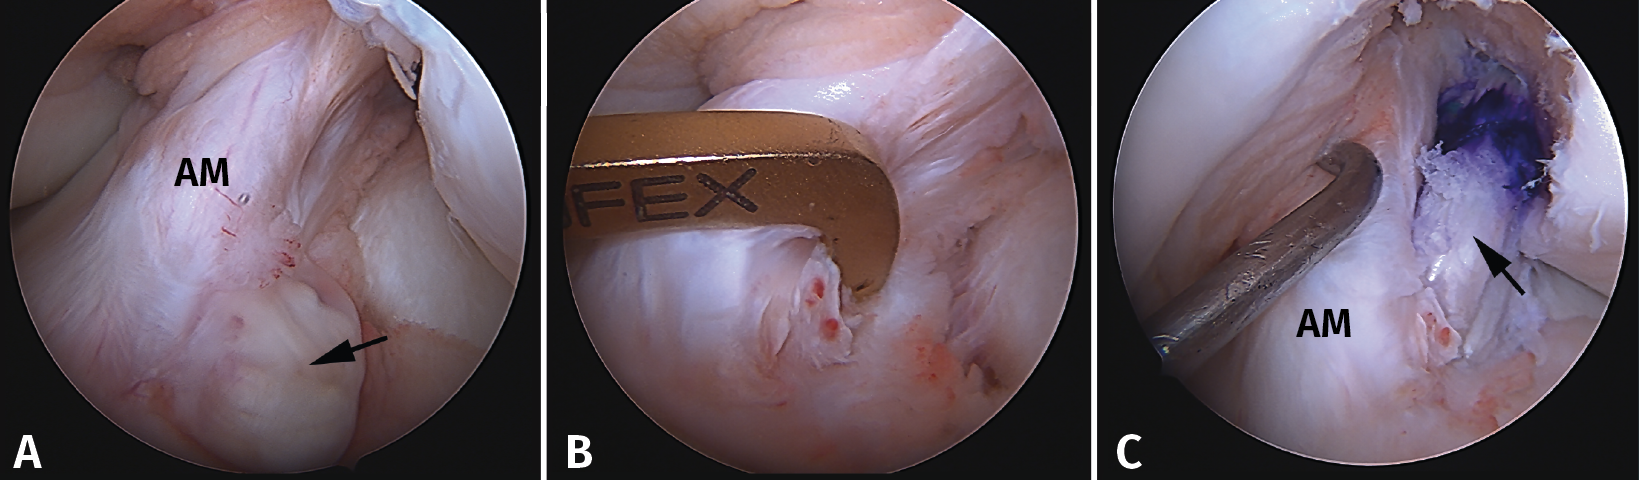

La reconstrucción selectiva del fascículo afectado sigue los principios básicos de la reconstrucción clásica anatómica del LCA (Figuras 9 y 10). Los autores realizan 3 portales: un portal anterolateral, lo más proximal posible con el fin de evitar la almohadilla grasa infrapatelar de Hoffa y tener una visión panorámica de toda la articulación; un portal AM alto y parapatelar, que utilizaremos como portal de visión y que nos va a permitir una mejor visualización de la huella anatómica femoral; y un portal AM accesorio, lateral al cóndilo femoral medial e inmediatamente superior al menisco interno, desde donde realizaremos el brocado del túnel femoral mediante técnica de manos libres(8). Otros autores recomiendan la realización del túnel femoral mediante técnica outside-in, considerando que ello facilita la realización del brocado femoral sin dañar las fibras del fascículo intacto(4).

Figura 10. Plastia de reconstrucción selectiva unifascicular (fascículo posterolateral –PL–). A: imagen artroscópica de la rodilla izquierda desde el portal anterolateral. Se evidencia una rotura completa crónica del fascículo PL con remanente tibial (flecha) e integridad del fascículo anteromedial (AM); B: imagen artroscópica de la rodilla izquierda desde el portal anterolateral. Colocación de la guía tibial tomando el remanente como referencia en una reconstrucción selectiva del fascículo PL; C: imagen artroscópica desde el portal AM que muestra la plastia de reconstrucción selectiva-aumentación del fascículo PL con autoinjerto de isquiotibiales (flecha).

Técnicamente, en la reconstrucción selectiva del fascículo AM o PM es fundamental reproducir la huella anatómica, tanto en el fémur como en la tibia. La mejor referencia para conseguir una posición correcta es localizar el remanente del fascículo roto(33).